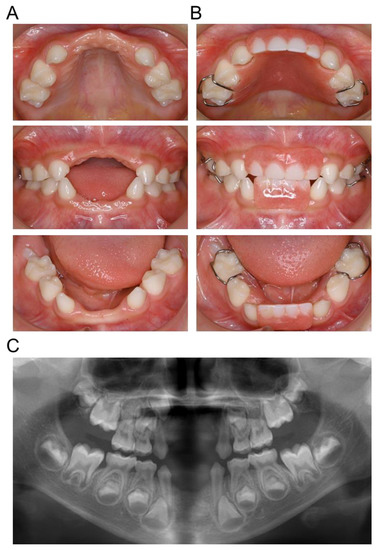

2. Case Presentation